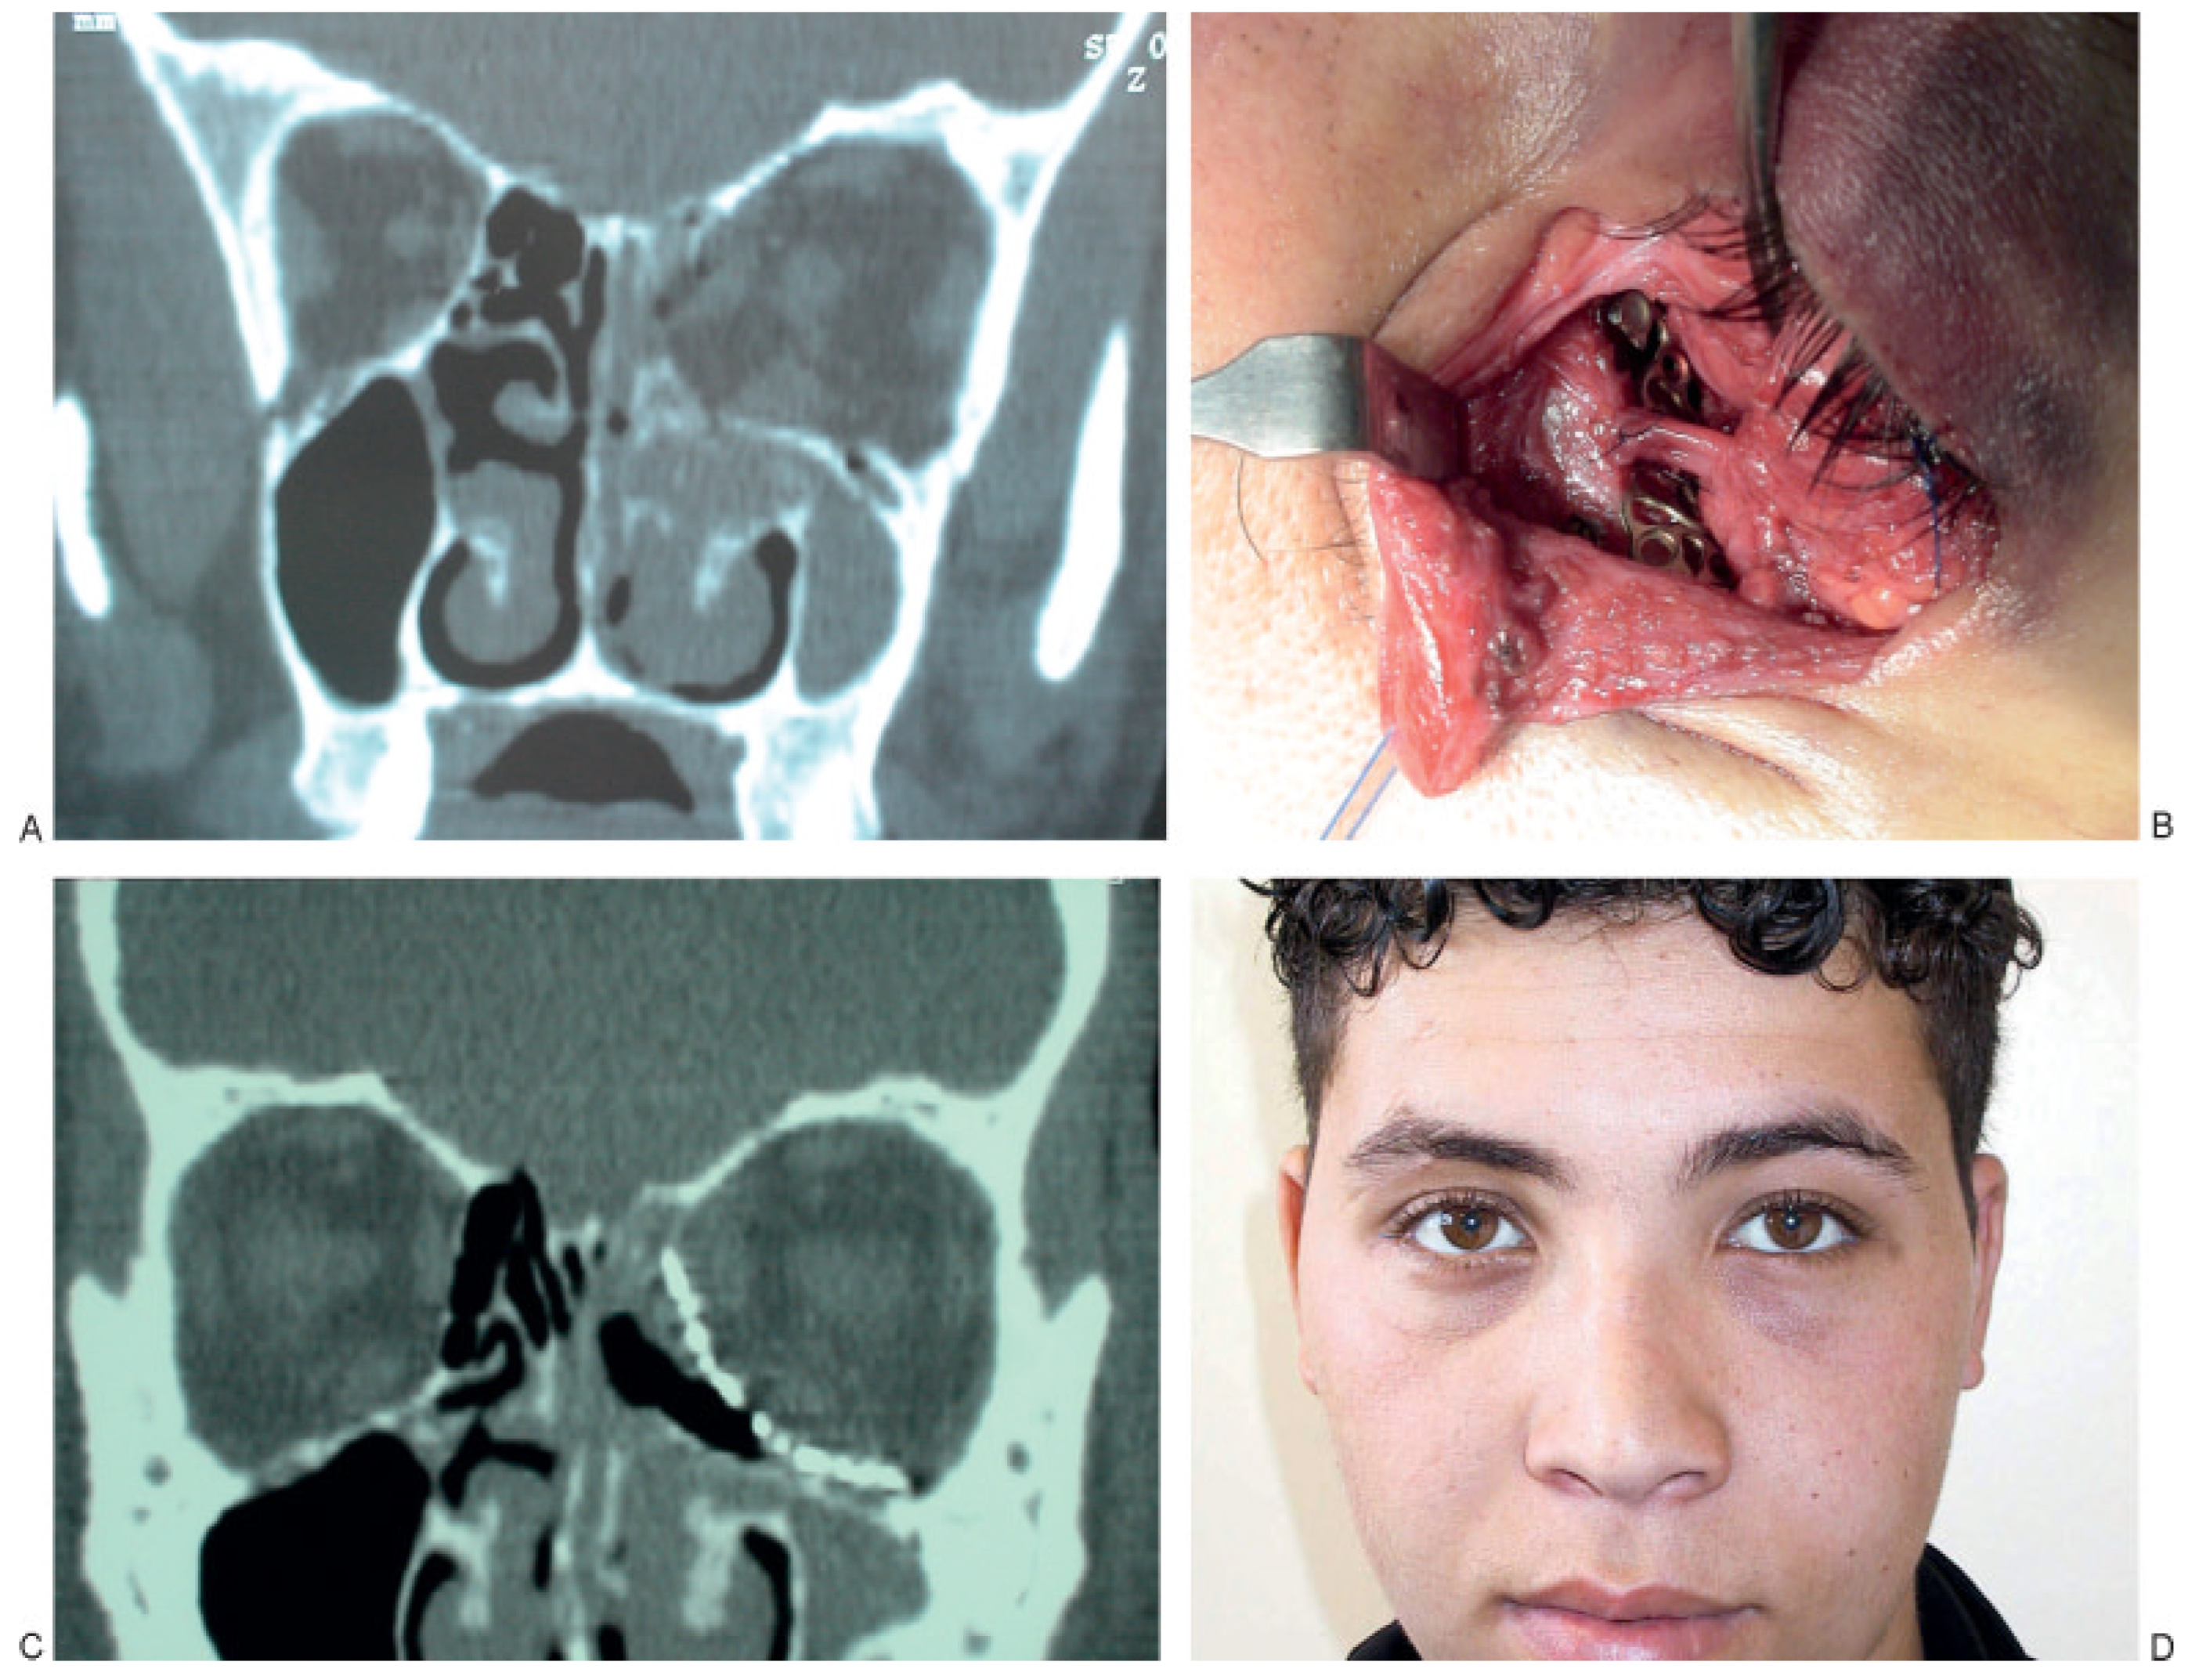

:SURGICAL TECHNIQUE

RESULTS